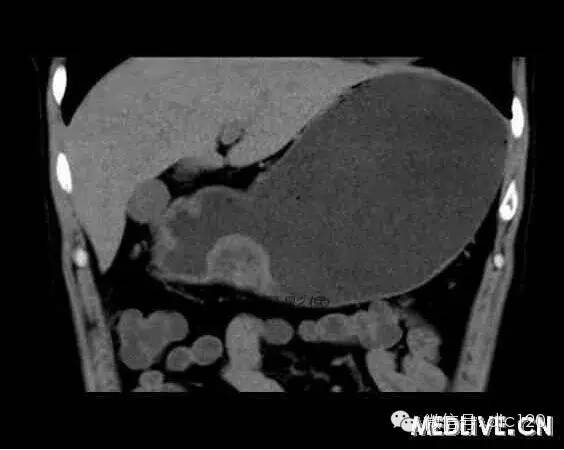

男,36歲,間斷性返酸噯氣3年,3個月前出現(xiàn)上腹疼痛,饑餓時加重。圖1-3為CT平掃,圖4-6分別為CT增強(qiáng)掃描的動脈期、門脈期和延遲期。

CT檢查可見胃幽門前區(qū)胃小彎側(cè)胃壁局限性增厚、隆起或伴凸向胃腔內(nèi)的小結(jié)節(jié)灶,寬基地,境界光整,注射對比劑,增強(qiáng)掃描后,CT值可達(dá)50HU以上,與正常胰腺強(qiáng)化相仿。

胃迷走胰腺大多位在距幽門1-6cm的胃竇胃大彎側(cè),粘膜下層內(nèi),為1-3cm大小的病灶。 與胃壁以寬基底相,增強(qiáng)掃描病灶表面覆蓋的黏膜明顯強(qiáng)化且連續(xù),病灶內(nèi)無明顯壞死,病變強(qiáng)化方式類似于正常胰腺組織;當(dāng)病灶出現(xiàn)邊緣臍凹征或中央導(dǎo)管征時,對EP的診斷具有一定的特異性。